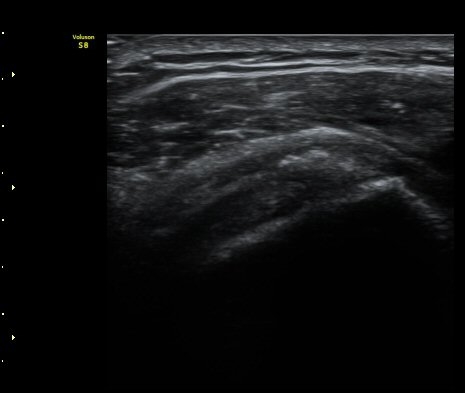

±Ø»ó°Ç ¸»´ÜºÎ Á¾´Ü¸é°Ë»ç¿¡¼­ ±Ø»ó°Ç°ú Á¡¾×³¶³» ¼®È¸È­°¡ °üÂûµÈ´Ù(±×¸² 4, 5).